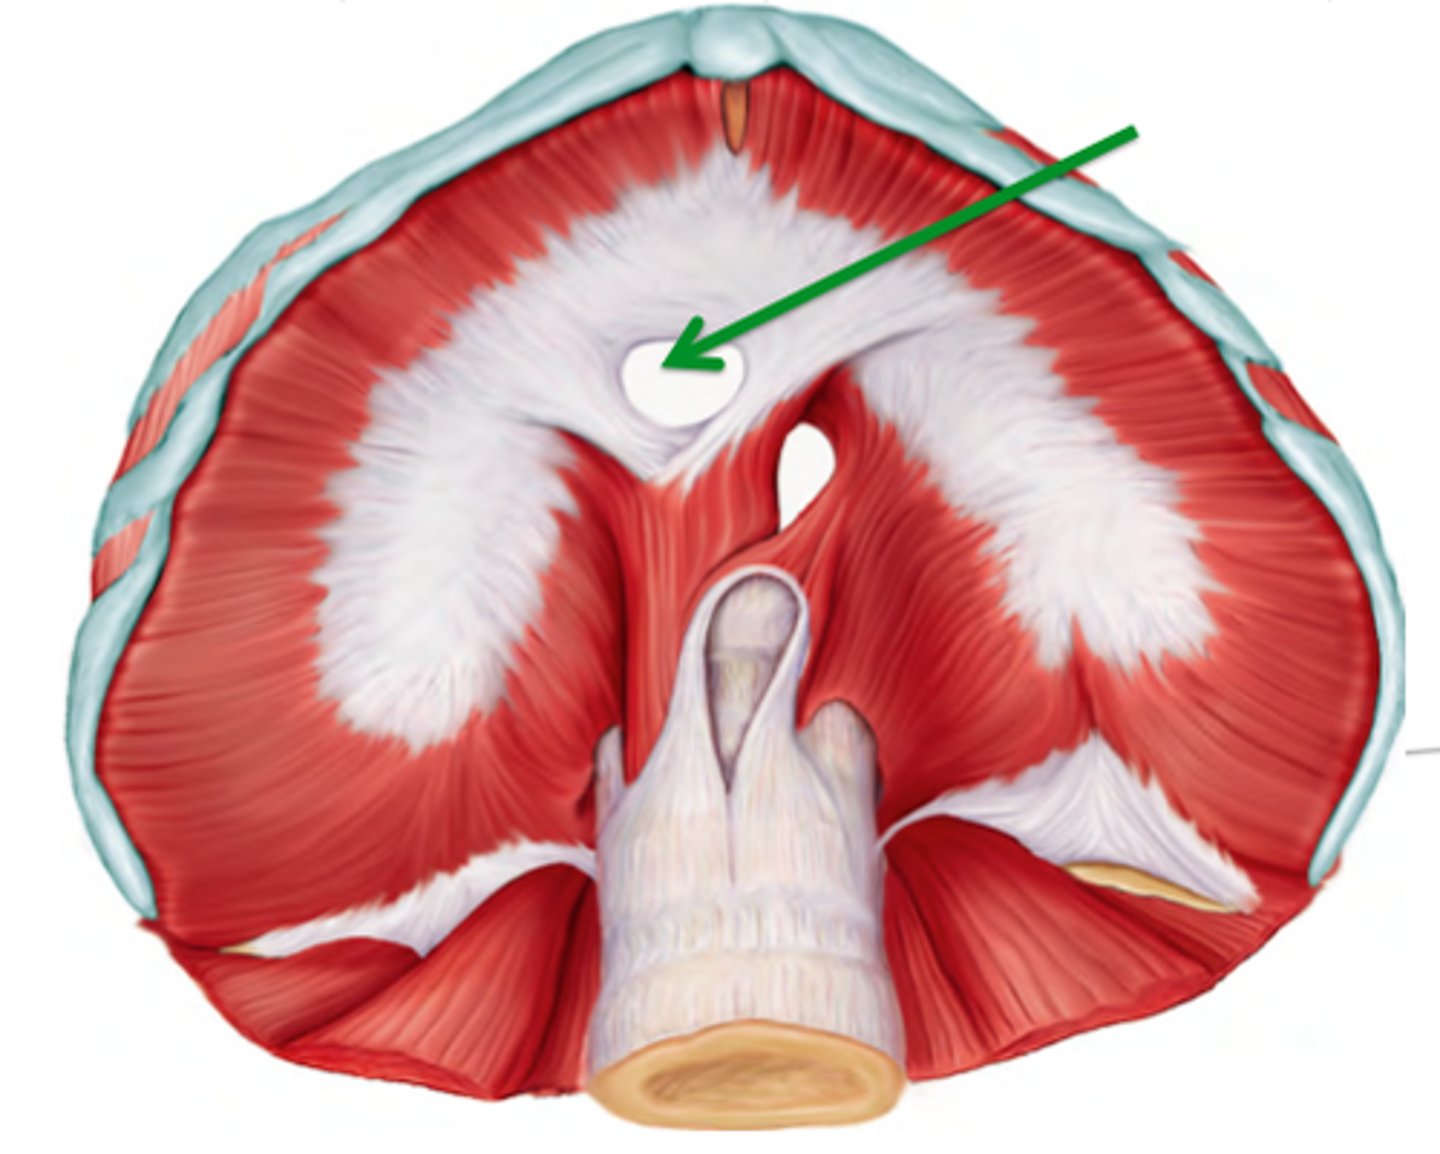

caval foramen

carries the inferior vena cava from the abdomen to the thorax to empty blood into the right atrium of the heart